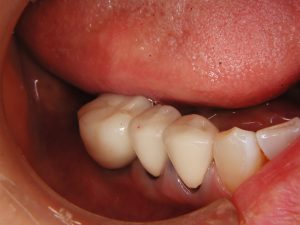

2016年6月にサイナスリフトをおこなった症例(30…

ストレスマネージメントとしての睡眠時のはぎしりは時として、咬合の崩壊をもたらします。 30代であれば、奥歯の再生とスムーズな歯ぎしりの誘導は、精神的にも全身の健康にも及ぼす効果は計り知れません。それほど奥歯の再生は重要です。 上あごの骨が無いところにインプラントを埋入しなければなりません。とる…